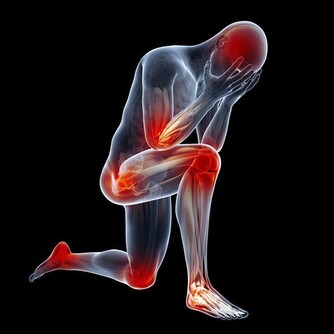

稍一運動就氣喘

男人向來比女人運動細胞發展得好,在各種體育項目中,男性都是比女性多的。但是現在的辦公室生活讓男人們的肌肉開始鬆懈,他們不再參加運動,甚至連周末都是在家補覺。有些男人稍一運動後就氣喘吁籲,而且持續時間比較長,這代表你的心臟調節能力越來越低,心臟的肌肉老化、彈性也在慢慢減弱,很容易出現心血管疾病。